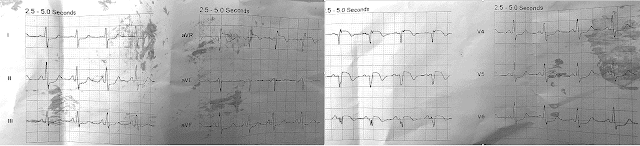

Две ЭКГ в сегодняшнем СЛУЧАЕ:

Рисунок 1: Я разметил две ЭКГ, показанные в сегодняшнем случае.

Исходная ЭКГ:

По словам доктора Смита, ЭКГ №1 была записана бригадой скорой помощи на следующий день после того, как эта 40-летняя женщина была выписана из больницы с диагнозом ИМбпST, но с нормальными коронарными артериями при катетеризации. На момент регистрации ЭКГ №1 ее симптомами были боль в груди и одышка, однако интерпретация этой первоначальной записи вызвала предупреждение об ИМпST. КЛЮЧЕВЫЕ находки на ЭКГ № 1 включают следующее:

- Синусовая тахикардия ~110/мин.

- Предположение о смещении оси вправо (неожиданно глубокий зубец S в отведении I).

- Заостренные зубцы P в нижних отведениях (не совсем удовлетворяющие амплитудному критерию а2,5 мм для истинной гипертрофии правого предсердия, но все же наводящие на размышления, учитывая клиническую ситуацию).

- Предположение о «перегрузке» ПЖ (как показано в СИНЕМ прямоугольнике — выпуклость сегмента ST с небольшой элевацией и довольно глубокой, симметричной инверсией переднего зубца Т).

- Элевация ST в отведении aVR.

- Диффузная депрессия ST (видна в 6 отведениях = II,III,aVF; и V4,5,6).

КОММЕНТАРИЙ: Хотя понятно, как комплексы QS с сопутствующим сводом и подъемом сегмента ST на ЭКГ № 1 могут вызвать беспокойство по поводу острого ИМ — катетеризация сердца, проведенная днем или двумя ранее, выявила нормальные коронарные артерии — и основным симптомом была одышка. Ввиду такой клинической картины сочетание данных ЭКГ, отмеченных выше, вместо этого должно немедленно вызвать беспокойство по поводу острой ТЭЛА.

- КЛЮЧЕВОЙ МОМЕНТ: Наиболее убедительные изменения ЭКГ видны внутри СИНЕГО прямоугольника, а именно, куполообразный ST с выраженной симметричной инверсией зубца Т в передних отведениях. У пациента с тахикардией и одышкой острая «перегрузка» ПЖ из-за ТЭЛА будет гораздо более вероятным объяснением этого явления, чем реперфузионные зубцы Т вследствие недавнего инфаркта.

2-я ЭКГ (после догоспитальной реанимации):

Как отмечалось выше, ЭКГ №2 представляла собой догоспитальную запись, выполненную после реанимации – предположительно, вскоре после ЭКГ №1. Бросающиеся в глаза находки следующее:

- Тахикардия сохраняется, но зубцы Р больше не наблюдаются! Общий ритм вполне регулярный, хотя и с некоторой нерегулярностью в одновременно регистрируемых отведениях V1,V2,V3.

- Комплекс QRS расширился, что соответствует БПНПГ. Зубец S в отведении I углубился, что соответствует либо БПВЛН, либо увеличению отклонения оси вправо вследствие острой «перегрузки» ПЖ.

- Несмотря на расширение QRS на ЭКГ № 2, я сильно подозреваю наджелудочковый ритм, поскольку начальное отклонение QRS (как направление, так и наклон) во многих отведениях очень похоже на начальное отклонение QRS на ЭКГ № 1 (?Узловая тахикардия?).

- Теперь виден S1Q3T3 (в период, прошедший с момента записи ЭКГ №1 — теперь мы видим определенный зубец Q в отведении III — и, несмотря на артефакт, кажущуюся симметричную инверсию зубца Т в отведении III).

- Паттерн qRR' виден в отведении V1. Хотя это соответствует БПНПГ (широкие терминальные зубцы S видны в боковых отведениях I и V6), qR в V1, вероятно, является индикатором повышенного давления в малом круге из-за серьезной «перегрузки» ПЖ.

- Несмотря на артефакт, присутствует инверсия нижнего и переднего зубца Т, указывающая на «перегрузку» ПЖ.

- Элевация ST в отведениях III и aVR.

КОММЕНТАРИЙ: Учитывая, что ЭКГ № 2 была записана после остановки сердечно-легочной деятельности, я интерпретировал эту запись как демонстрацию прогрессирования нарушений со времени ЭКГ № 1 и практически подтверждение массивной острой ТЭЛА как причины.